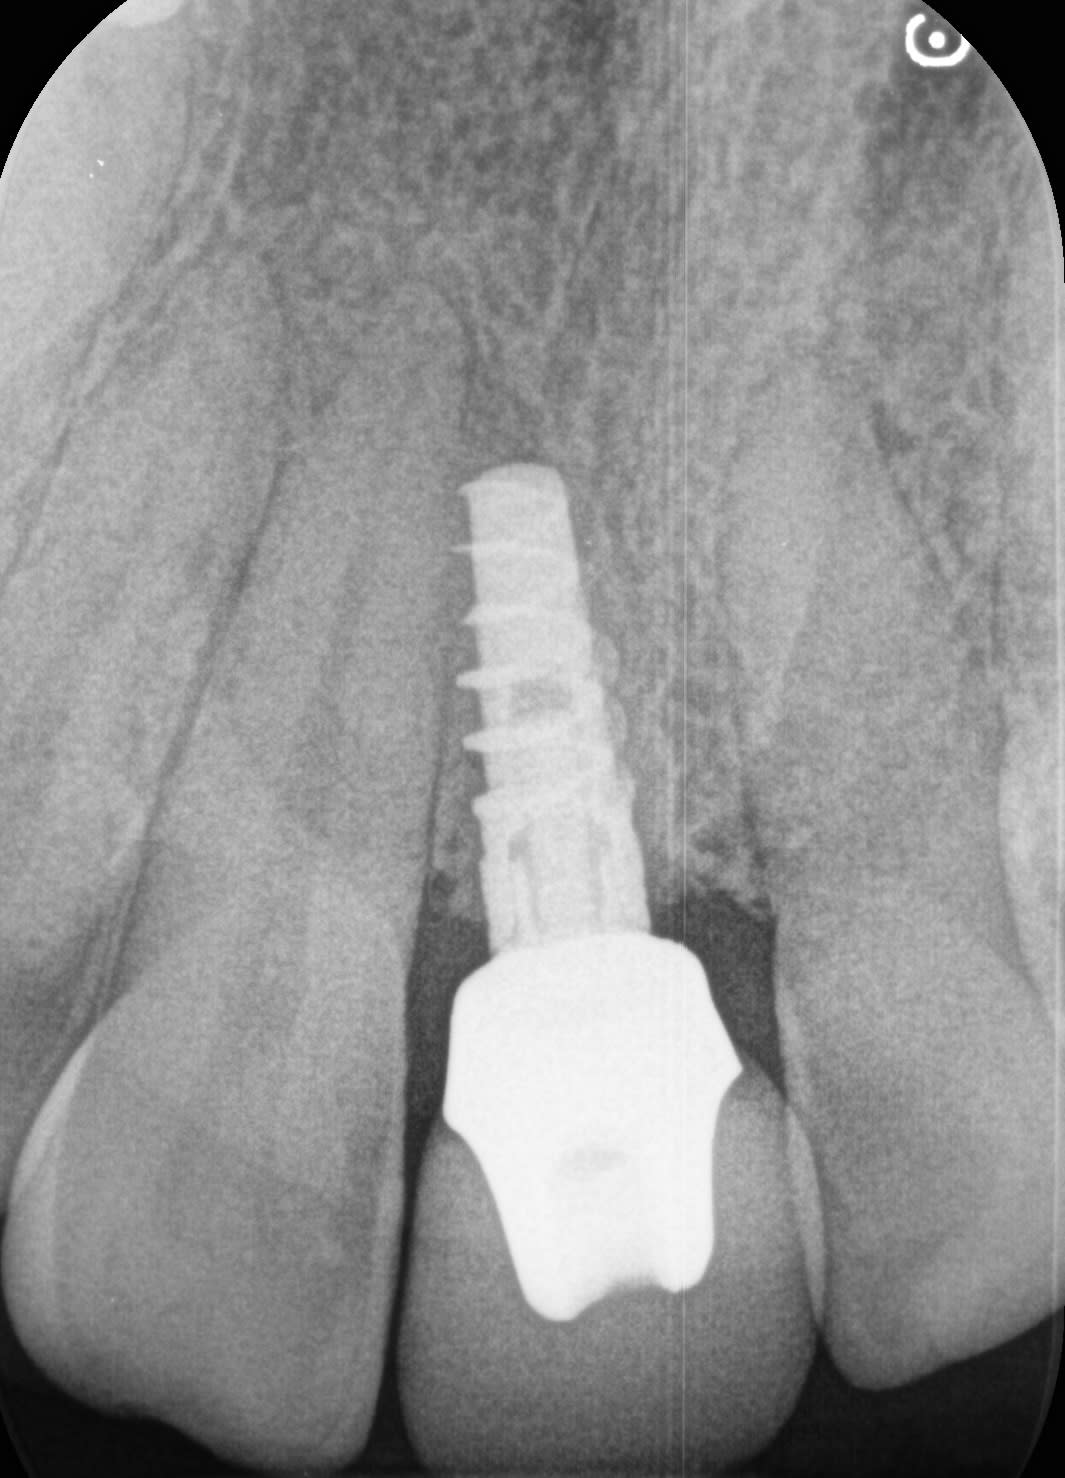

Patiente souhaitant reprendre sa couronne sur sa centrale.

J'ai pensé à un Nobel active ?

Si cette radiographie vous parle merci de m'éclairer !

Nobel, non, çà c'est à 95% de certitude une connexion type Zimmer....

donc un implant "spirale" quelconque....genre TOV ou Alphabio